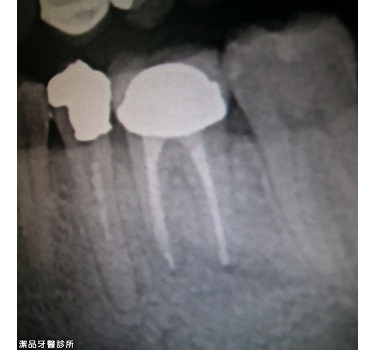

根管重新治療案例-002

案例簡述:

根管重新治療

兩年後 精準的根管治療後不再發炎,齒槽骨長回來了!